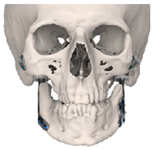

| 1 | 71 | FT-M0 | ![]() | Temporal bone, aygomatic arch, glenoid fossa and condyle | Unalloyed titanium mesh temporal and zygomatic backing capping the UHMWPE fossa | Cobalt-chromiun-molybdenum alloy condylar head and Titanium alloy body | Skull component: 62.0 mm titanium screws. Manibular component: 82.7 mm titanium screws |